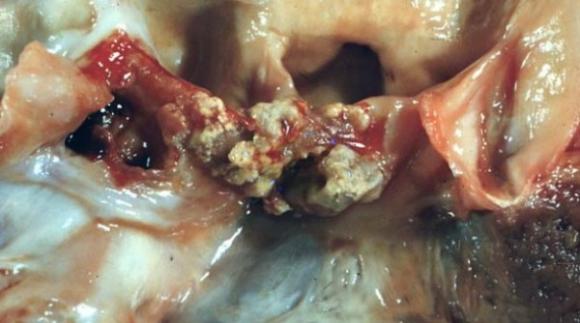

Problemas que genera la inflamación interna del corazón podrán evitarse mediante una nueva técnica desarrollada por médicos argentinos. La nueva técnica consiste en un método de diagnóstico rápido para la...